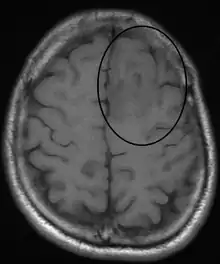

Oligodendroglioma arise mainly in the frontal lobe and in 50–80% of cases, the first symptom is the onset of seizure activity, without having any symptoms beforehand.[1] Headaches combined with increased intracranial pressure are also a common symptom of oligodendroglioma. Depending on the location of the tumor, many different neurological deficits can be induced, including, but not limited to, visual loss, motor weakness and cognitive decline. A computed tomography (CT) or magnetic resonance imaging (MRI) scan is necessary to characterize tumor size, location, and hetero- or homogeneity. Final diagnosis relies on biopsy and histopathologic examination of the tumor mass.[1]